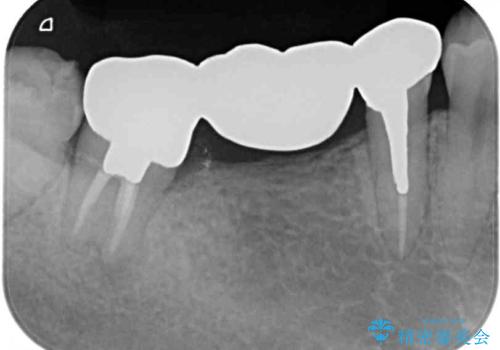

- 全顎的に銀歯が多く、その中でも目立って気になる奥歯のブリッジをセラミックに替えたいとのことで来院された患者様です。

上顎のブリッジを先に交換したものの、今度は下顎のブリッジ支台歯が食事もできないほど痛み出したとのことでした。

銀歯の適合が悪く、土台の歯に虫歯多く残っていたので、痛む歯の根管治療とファイバーコアによる土台植立を行い、フルジルコニア製ブリッジを装着することとしました。